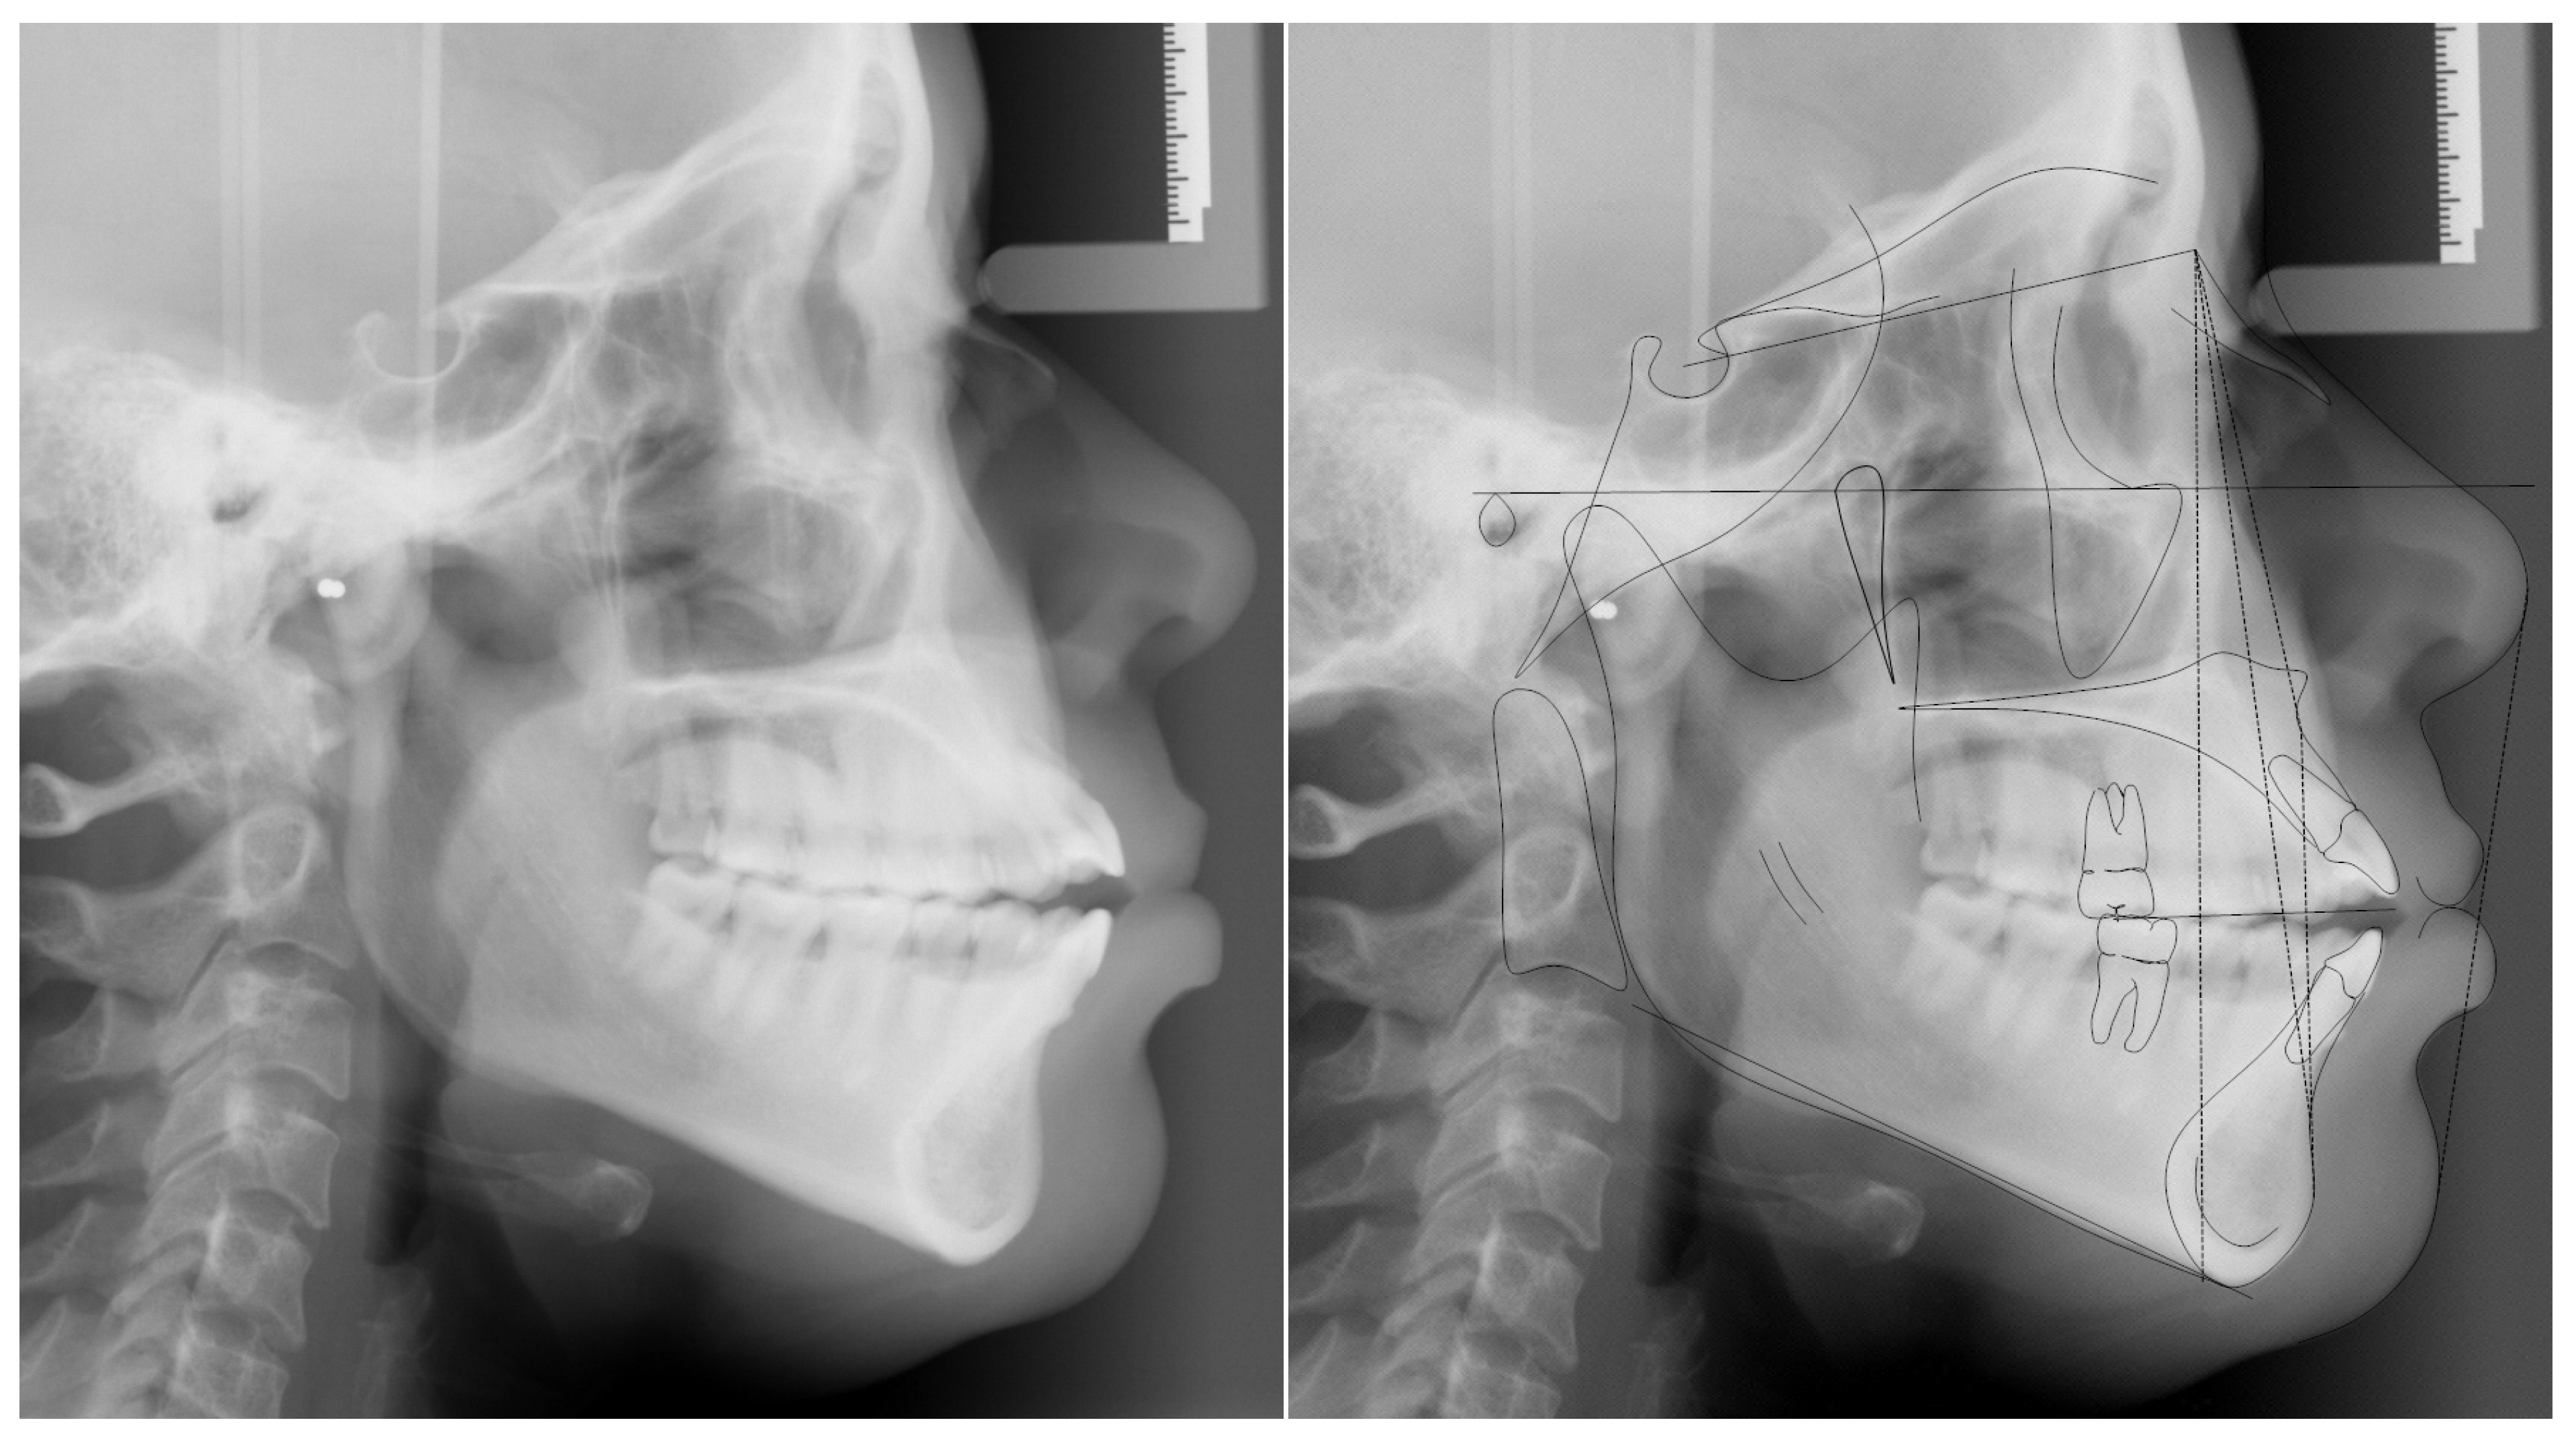

Cephalometric analysis revealed a mild class II skeletal relationship (ANB = 4.9 deg) with protrusive upper and lower jaws (SNA° = 89.6°, SNB° = 84.7°), normal mandibular plane (SNA-MP° and FMA° = 38.7° and 26.3°, respectively), proclined maxillary incisors (U1-SN = 119.6°) and protruded and proclined mandibular incisors (L1-NB = 11 mm, IMPA = 97.7°) (Figure 3 and Table 1).

Figure 3.

Pretreatment cephalometric radiograph and tracing.